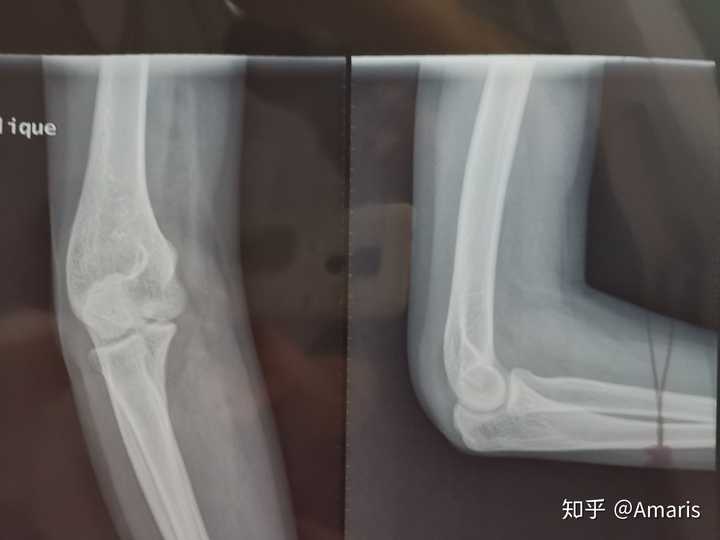

急诊拍x线片两张|作者供图

晋先生拍的片子显示骨折